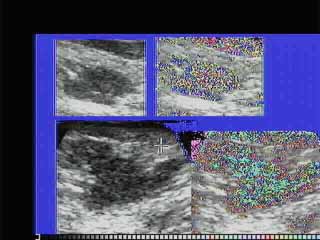

Oι τελευταίες 4 απεικονίσεις έγιναν με ειδικό για μαστό ηχοβολέα linear, εναλλασσομένης συχνότητος 7,5-10ΜΗΖ.